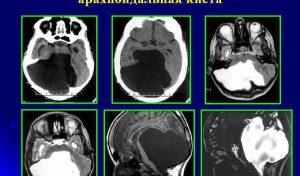

Размеры арахноидальной кисты: норма и когда нужна операция?

В этой статье вы узнаете об особенностях арахноидальной кисты головного мозга, причинах и симптомах патологии, лечении и профилактике, а также прогнозе. Арахноидальная киста — это врожденная или приобретенная полость со спинномозговой жидкостью между поверхностью мозга и паутинной оболочкой. Общие данные Своим названием он обязан расположению в паутинной оболочке. Паутинная оболочка на месте кисты утолщена и …